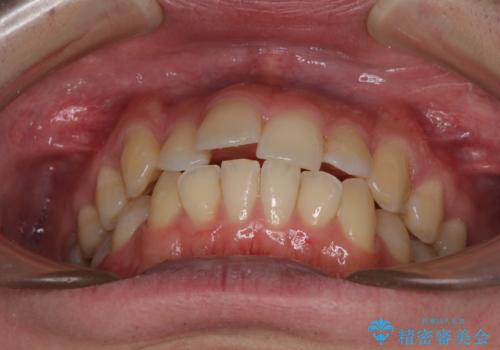

- 上下前歯のデコボコを気にして来院された患者様です。

口元はやや突出感がありましたが抜歯矯正をするほどではないため、舌突出癖を改善するトレーニングをしっかりと行っていただき、現在よりも唇が閉じやすい位置に仕上げていくこととしました。